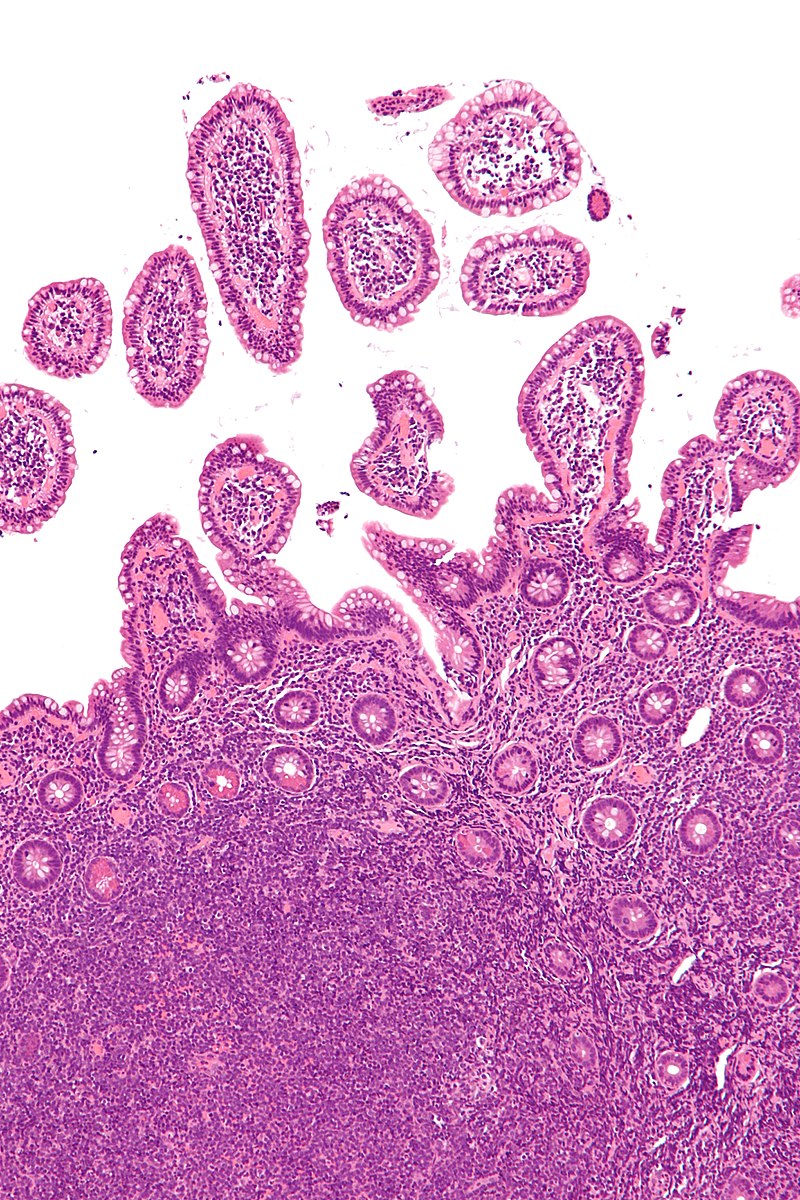

Mucosa associated lymphoid tissue (MALT) lymphoma is a mucosal-site marginal zone lymphoma.

Treatment for H Pylori may cause the gastric MALT lymphoma to regress.